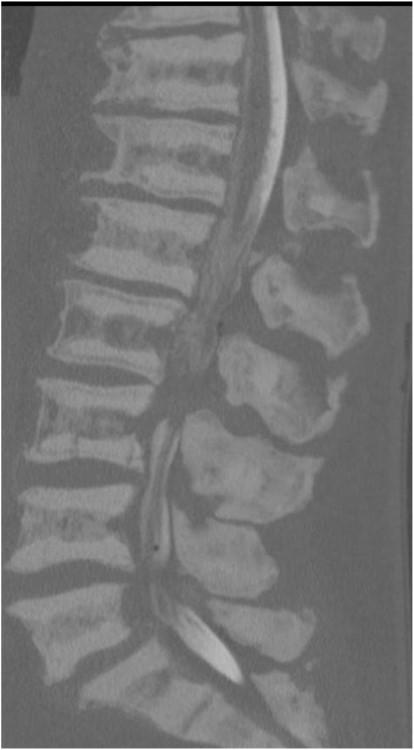

Six months later, he complained about lumbar pain which irradiated into the right thigh and knee. A CT scan of the lumbar spine showed multiple lumbar spine stress fractures, and CT myelography showed complete obstruction at L2–3 level (Figs 4 and 5). Conservative therapy was ineffective. Therefore, the patient was transferred to a spinal center. There he underwent L2–L3 decompression with short-term effect because decompression resulted in instability. 360° spondylodesis was done; however, it resulted in non-union, and the material was removed (Fig. 6).

Sagittal view of CT lumbar spine myelography. Note also the density of sclerotic bone.